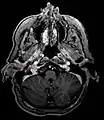

Micrograph of a carotid body tumor

Glomus jugulare tumor

Ectopic functional paraganglioma (glomus jugulare) in a patient with VHL. T2 weighted MRI at the same location demonstrates a high signal mass consistent with a paraganglioma. Extra adrenal paragangliomas can be found in VHL (arrow).